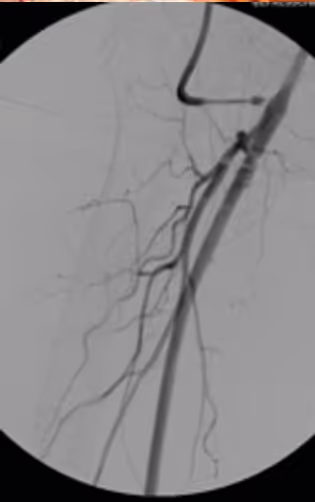

To perform a femoro-popliteal bypass (Dacron or PTFE, 6-8mm)to popliteal artery pars I

Create proximal side-to-end anastomosis in running suture technique

Create distal end-to-end anastomosis in running suture technique

Proximal anastomosis (side-to-end)

Distal anastomosis (end-to-end)